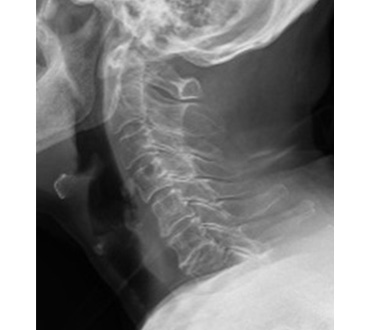

一般撮影室

主にレントゲン写真と呼ばれていてX線を利用し、胸部、腹部、骨などの撮影をします。人体にX線をあて透過したX線をコンピュータで処理し画像にします。迅速に画像を提供できることから、日常の診断に最も多く利用されている検査です。